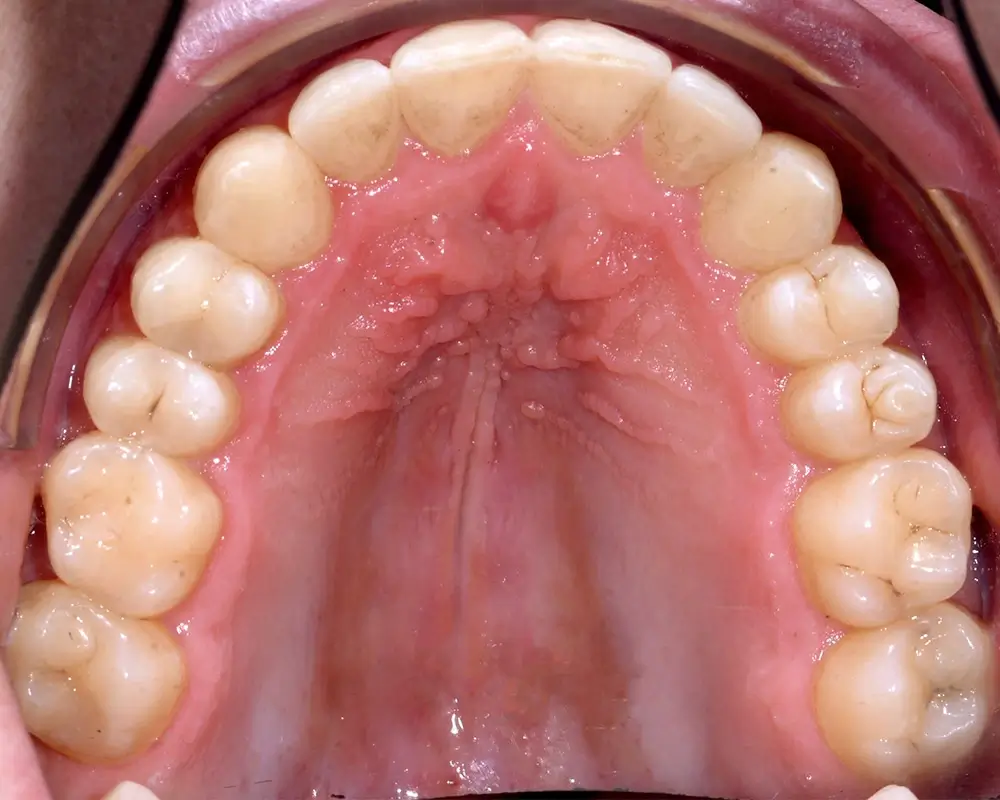

Перекрестный прикус - Кейс 5

Эффективность устранения дефекта прикуса посредством элайнеров FlexiLigner.

27

Количество кап НЧ

25

Количество кап ВЧ

Результаты лечения